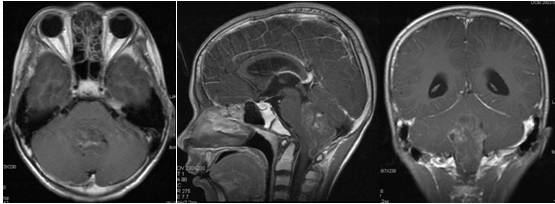

术后第2天,患者一般情况良好,未诉明显不适。术后常规复查头颅CT,提示四脑室肿瘤术后改变,术区少许积血;术后复查头颅MRI增强:术区轻度水肿,增强扫描未见明显异常强化结节(图2)。

图2. 术后CT平扫,四脑室肿瘤术后改变,术区少许积血。术后复查头颅MRI增强:术区轻度水肿,增强扫描未见明显异常强化结节。